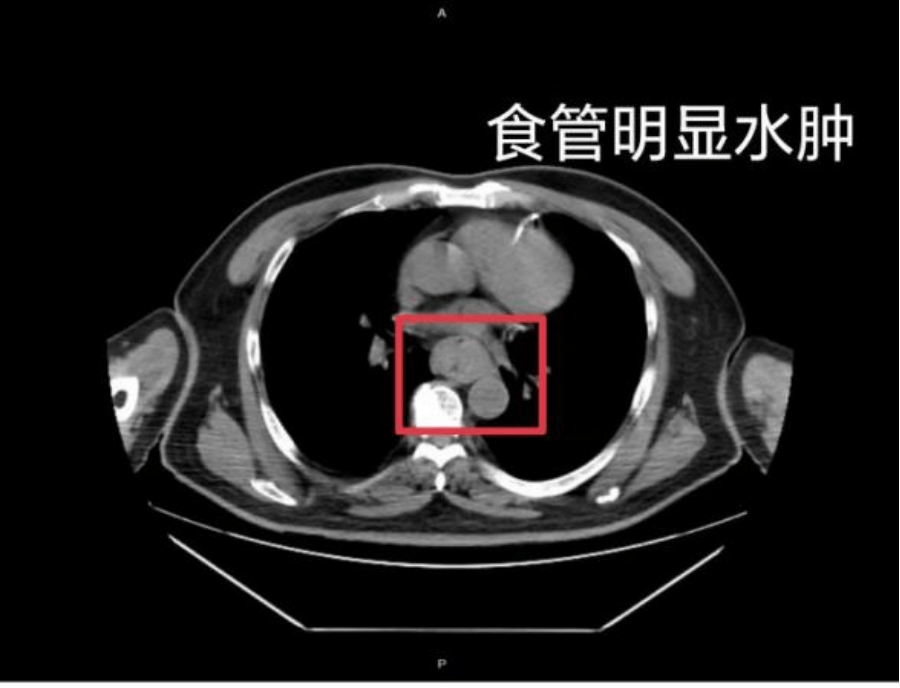

这样的情况并非个例,同样在近日,福州一位网友分享了自己因吃了一碗很烫的福鼎肉片导致呕血,并查出食管水肿的经历以太坊贸易。

据网友回忆,“自己去厕所尝试呕吐时,直接呕出了血,一大口鲜血从嘴里喷出,总共吐了两次以太坊贸易。”CT 结果显示,他的食管全部出现水肿损伤。